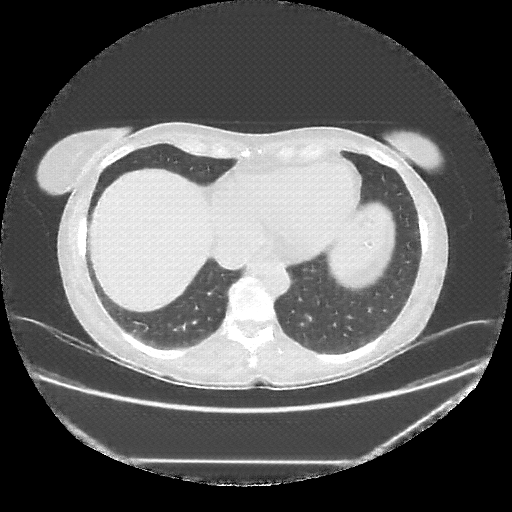

Image Grid

4Γ—3 grid: Rows show different image types (Original NATIVE, Reconstructed NATIVE, Original VENOUS, Generated VENOUS), Columns show windowing techniques (No Window, Lung Window, Mediastinum Window)

Reconstructed NATIVE CT scan (cycle consistency)

Full window (WL 1023.5, WW 4095 β†’ Low βˆ’1024, High +3071)